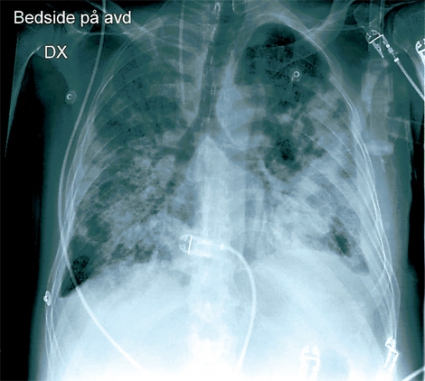

Patienten kraftigt försämrad. På kvällen den sjunde dagen efter inläggning försämrades patienten med dyspné, sjunkande saturation och tryck över bröstet. Hb sjönk från 113 till 74 g/l. Akut lungröntgen visade en bild förenlig med lungödem alternativt lungblödning. Patienten försämrades ytterligare, och han intuberades och lades i respirator. Ny lungröntgen efter att central venkateter lagts in visade ingen pneumotorax, däremot progress av lungförändringarna, mest uttalat på vänster sida med pleuravätska (Figur 3). Ny bronkoskopi visade inget synligt blod i bronkerna men rikligt med klart sekret. Flera timmar senare blev patientens tryck instabilt. Septikemi misstänktes och han fick tobramycin och trimetoprim–sulfametoxazol intravenöst. Då malignitet var en sannolik differentialdiagnos påskyndades svaret från den cytologiska undersökningen av bronkoalveolärt lavage och borstprov. Denna visade endast ospecifik inflammation och inga maligna celler. Man gjorde även ett ultraljud av hjärtat, vilket var svårbedömt, men vänster kammare bedömdes fungera normalt. Det blev dock allt svårare att ventilera patienten i respiratorn. Han försämrades successivt med sjunkande syresättning och höga luftvägstryck och avled efter några timmar.